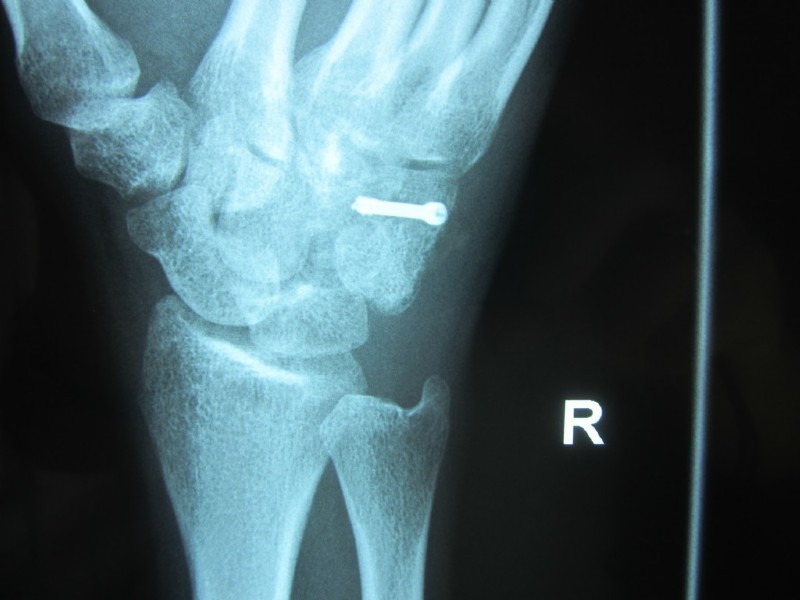

Fracture of the hamate bone

The young man (boxer) punched aggressively and once felt a sharp pain in the wrist.

After fitting and a 6 weeks cast, the patient was able to start training again.